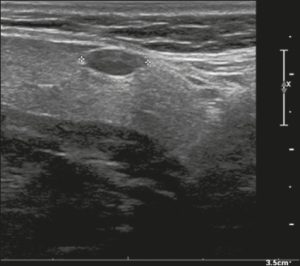

Ở đây, chúng tôi cung cấp các ví dụ minh họa việc áp dụng thực tế hệ thống ACR TI-RADS (Hình 18, 19, 20, 21). Các chú thích dưới hình mô tả chi tiết các mục đã được đánh giá và hiển thị điểm số trong ngoặc đơn.

Hình 21. Hình ảnh nhân giáp dạng đặc (2 điểm), giảm âm (2 điểm), cao hơn rộng (3 điểm), có đường bờ không xác định (0 điểm), và không có các ổ tăng âm hay bóng lưng (0 điểm). Do đó, tổng điểm là 7 điểm và mức độ nguy cơ được phân loại là TR5.